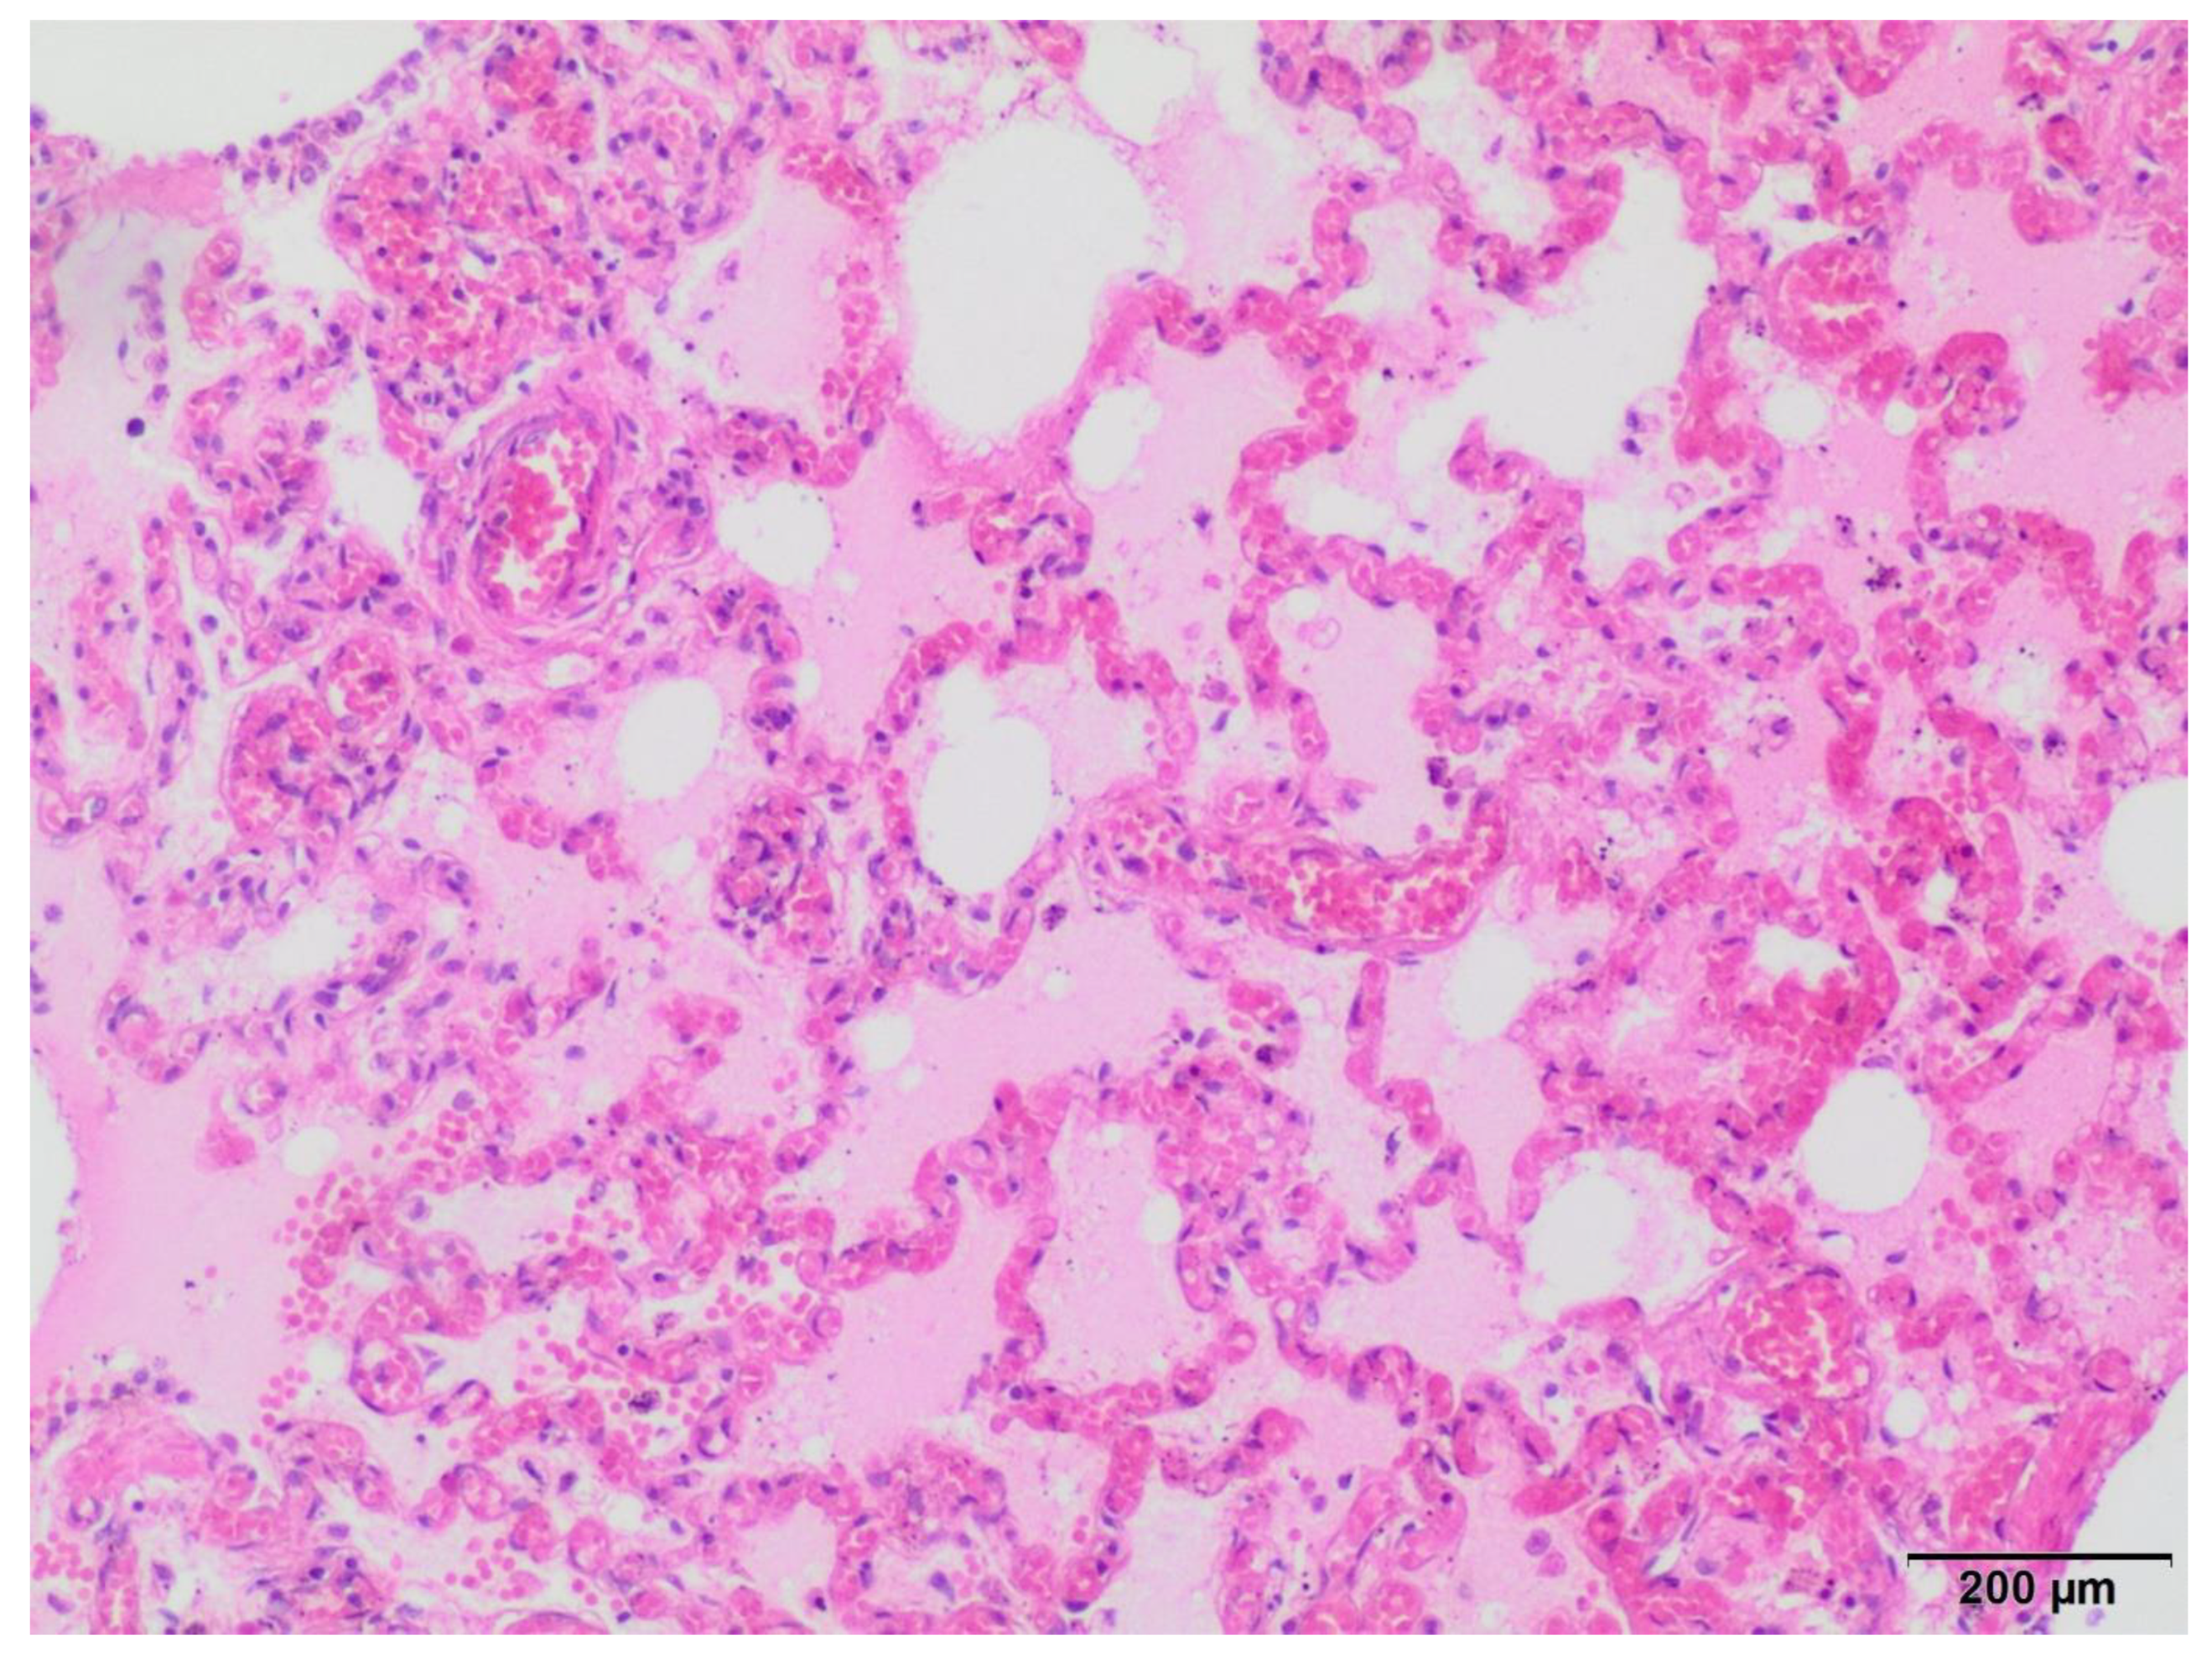

3.1. Anatomopathological and Histopathological Examination